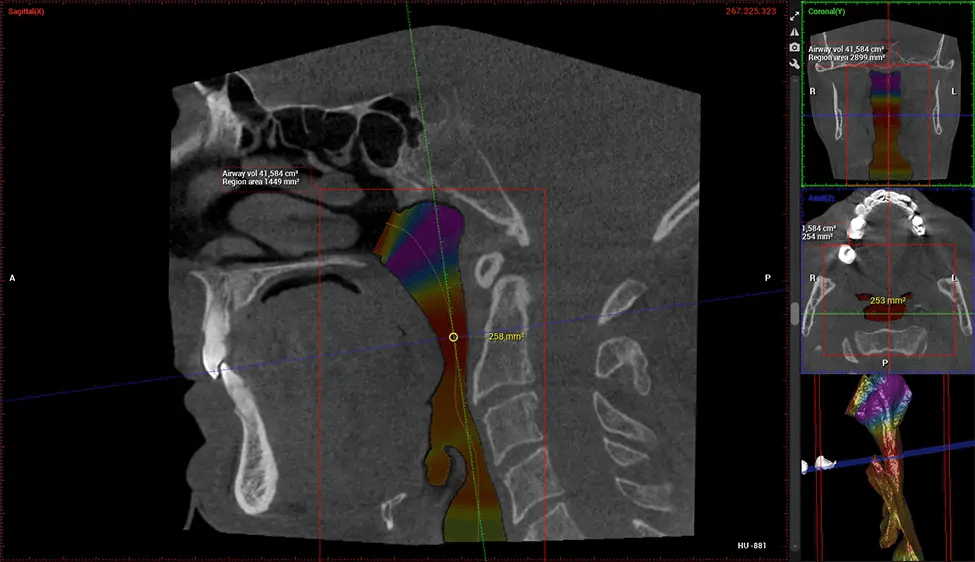

Planmeca Viso G7 CBCT ( Cone Beam CT Scan ) is designed to surpass the demands of industry leaders, specialists, and large institutions. It’s has a large ø25×30 cm sensor with four built-in cameras. It can capture unlimited volume sizes from a ø3×3 cm to a ø30x30cm volume capturing the skullcap through C7 on the cervical spine. The Planmeca Viso G7 offers the industry’s largest single volume scan of ø30×19 cm. It’s poised to handle advanced imaging modalities such as Planmeca ProFace® and Planmeca 4D™ Jaw Motion technology. The occipital head support allows an unimpeded view of facial tissue.

Planmeca is the only manufacturer clinically proven to dramatically reduce patient radiation without sacrificing image quality. Planmeca Ultra Low Dose™ achieves an average reduction in dose of 77% without a statistical reduction in image quality allowing doctors to incorporate 3D imaging into routine protocols with effective patient radiation often lower than 2D intraoral imaging. This increases patient care, allows doctors to diagnose more dentistry, and often earlier in disease progression, than with 2D imaging alone.

Our patented SCARA technology enables doctors to capture True Extraoral Bitewings that are as accurate at detecting caries as a 2D bitewing series, but with half the radiation dose. With our bitewings, doctors can view the apices of teeth on both jaws providing a more comprehensive view of the patients’ anatomy.